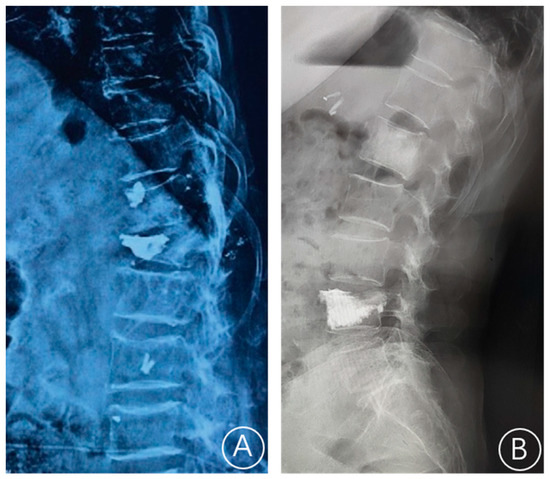

The X-ray film showed a rupture of the anterior cortex of the vertebral body and anterior displacement of bone cement (Figure 1). CT showed a rupture of the anterior cortex of the vertebral body, the anterior edge of the bone cement was more than 2 mm from the anterior edge of the vertebral body, and the bone cement moved forward. MRI examination showed vertebral collapse, and sagittal T1-weighted images and T2-weighted images of the fracture cavity showed abnormally low and high signal intensity, respectively [12]. A typical case is shown in Figure 2.

A 71-year-old female patient had recurrent low back pain and limited movement 3 years after L1 vertebroplasty. (A,B): Lumbar positive and lateral X-ray films scanning at 36 months after PVP showed L1 vertebral cement displacement and T12 vertebral compression fracture. (C–E): CT cross-section, sagittal plane, and coronal plane showed anterior cortex defect and bone cement displacement of the L1 vertebral body and compression fracture of the T12 vertebral body. (F–H): T1W1 showed low signal intensity, and T2W1 showed high signal intensity at the L1 vertebral body. (I,J): The positive and lateral positions of X-ray films showed that after posterior thoracolumbar bone graft fusion and bone cement enhanced internal fixation.